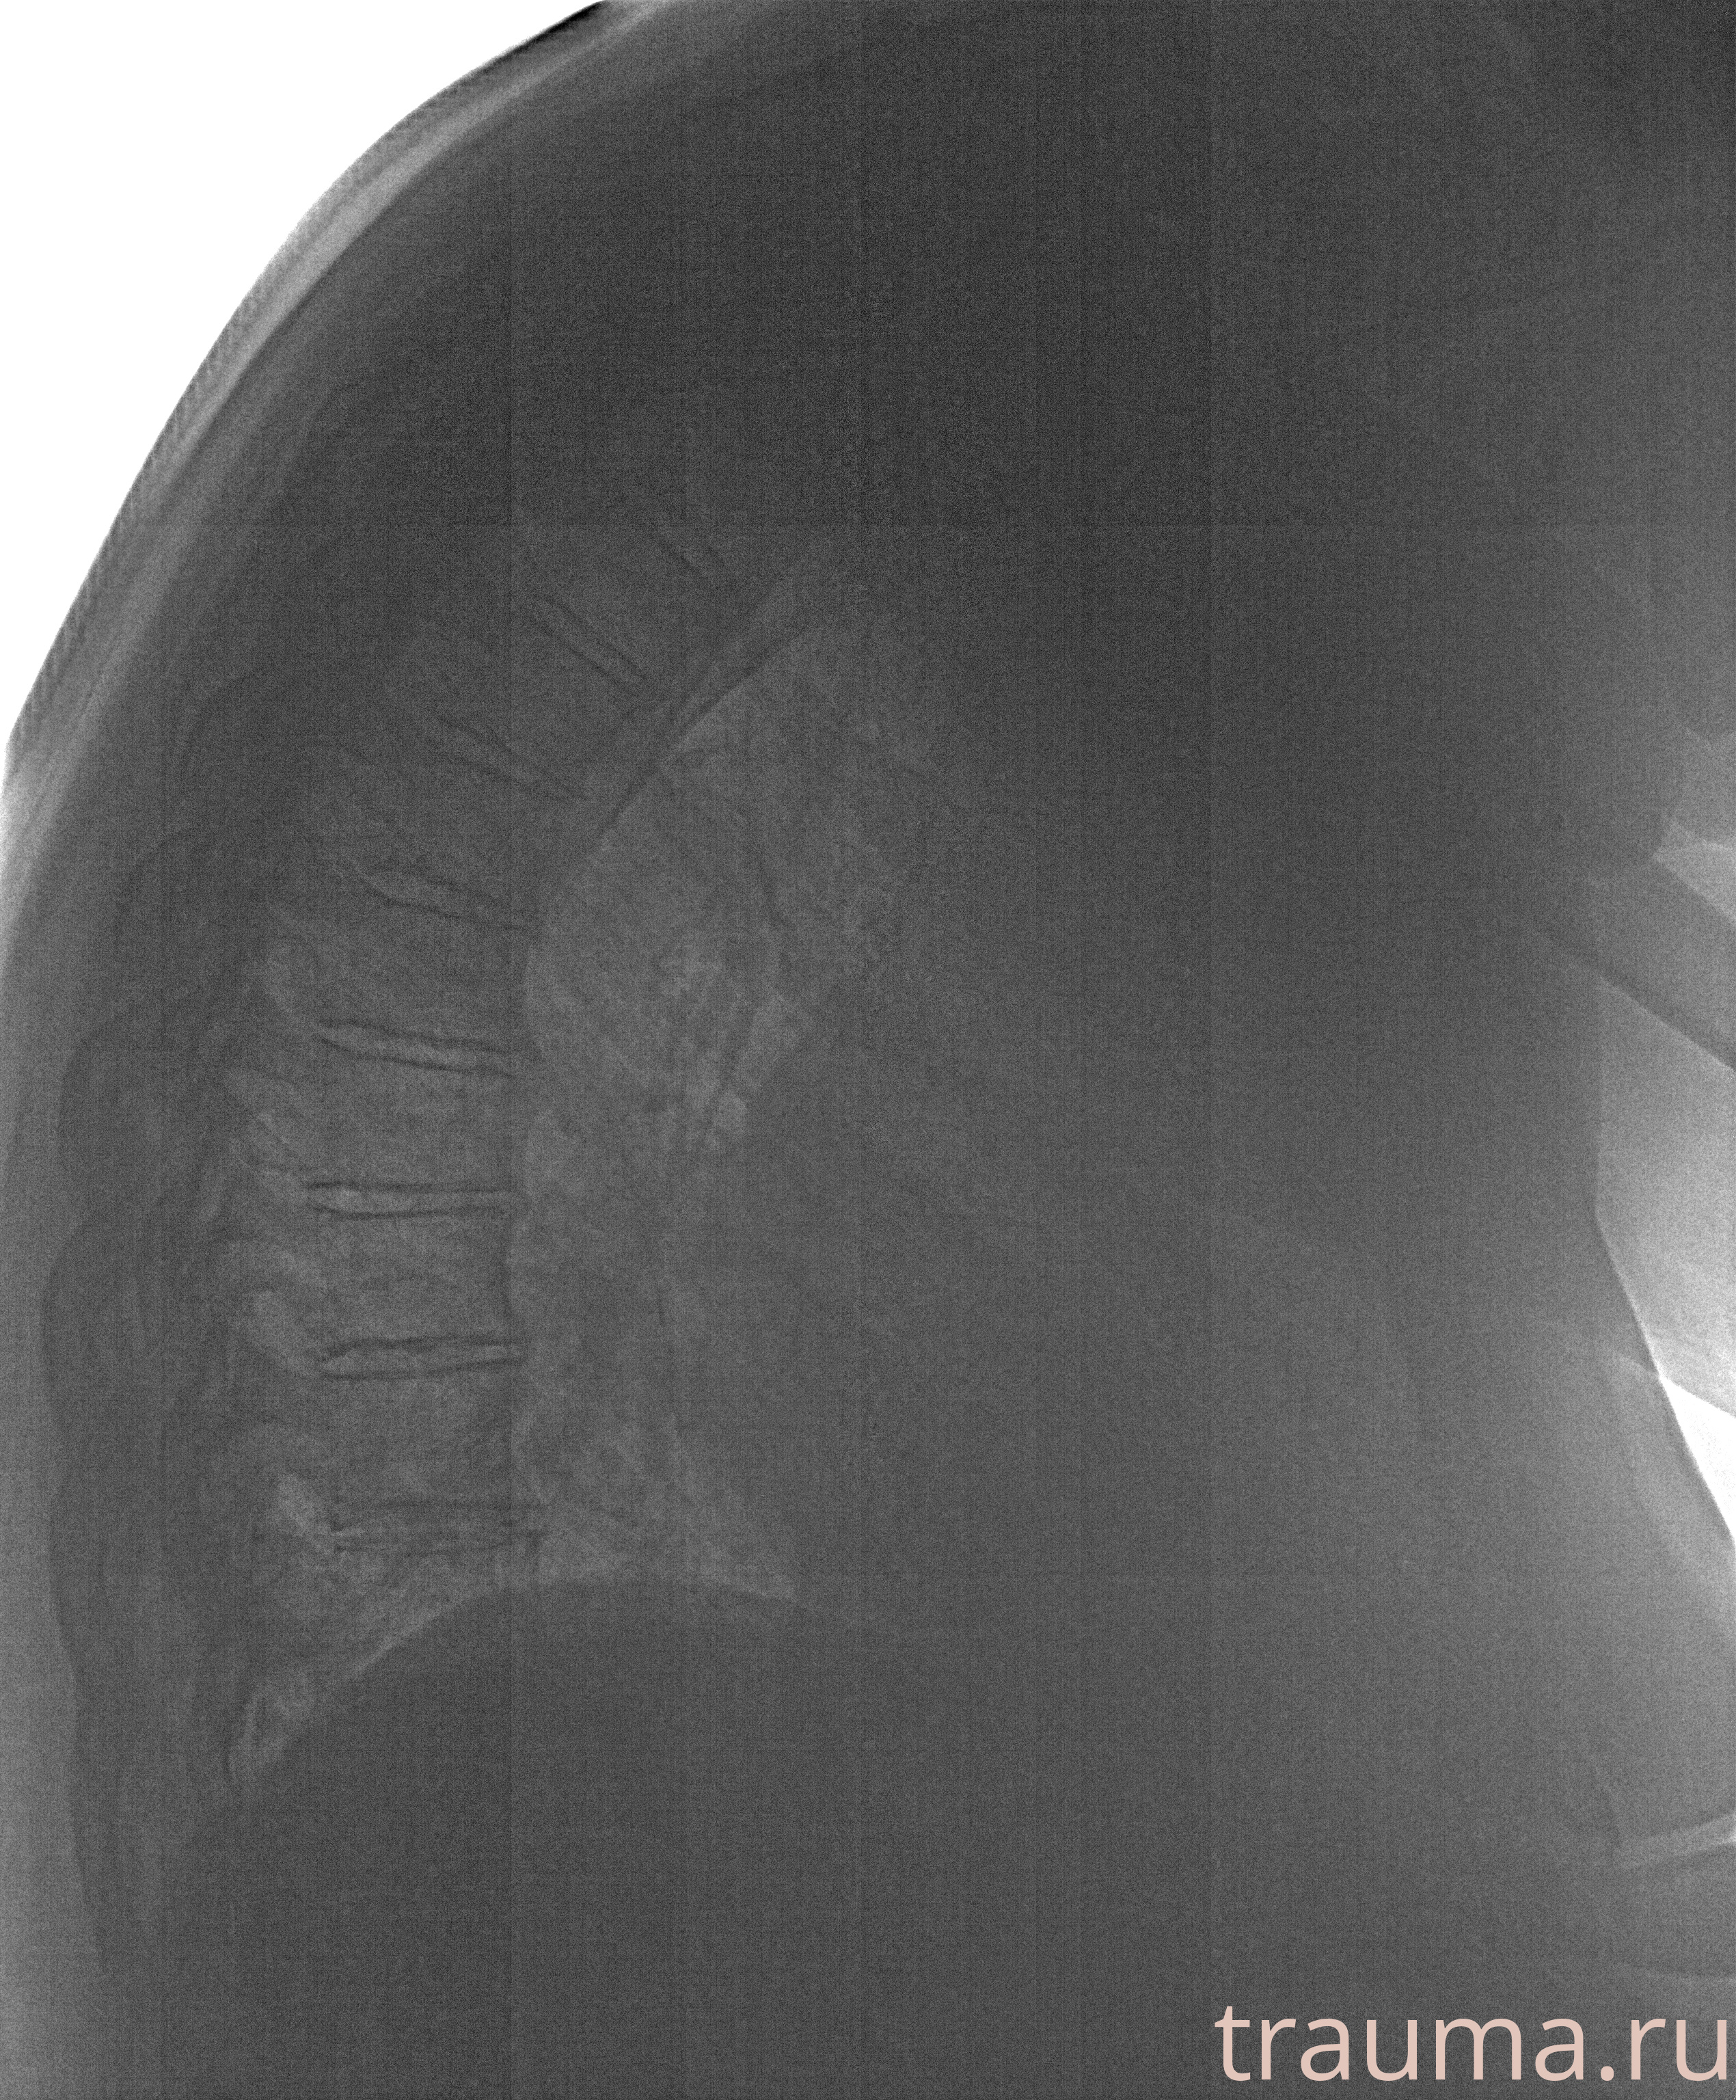

Рентгенограммы

Рентген на дому: по вашему адресу приезжает врач-рентгенолог, травматолог-ортопед с мобильным рентгеновским аппаратом, проводит диагностику травмы или заболевания, делает необходимые рентгенограммы, дает рекомендации по дальнейшему лечению. Получить качественные снимки в домашних условиях возможно благодаря уникальной методике, разработанной МосРентген Центром для института  Склифосовского

при переломе шейки бедра и пневмонии от компании МосРентген Центр - партнера Института имени Склифосовского